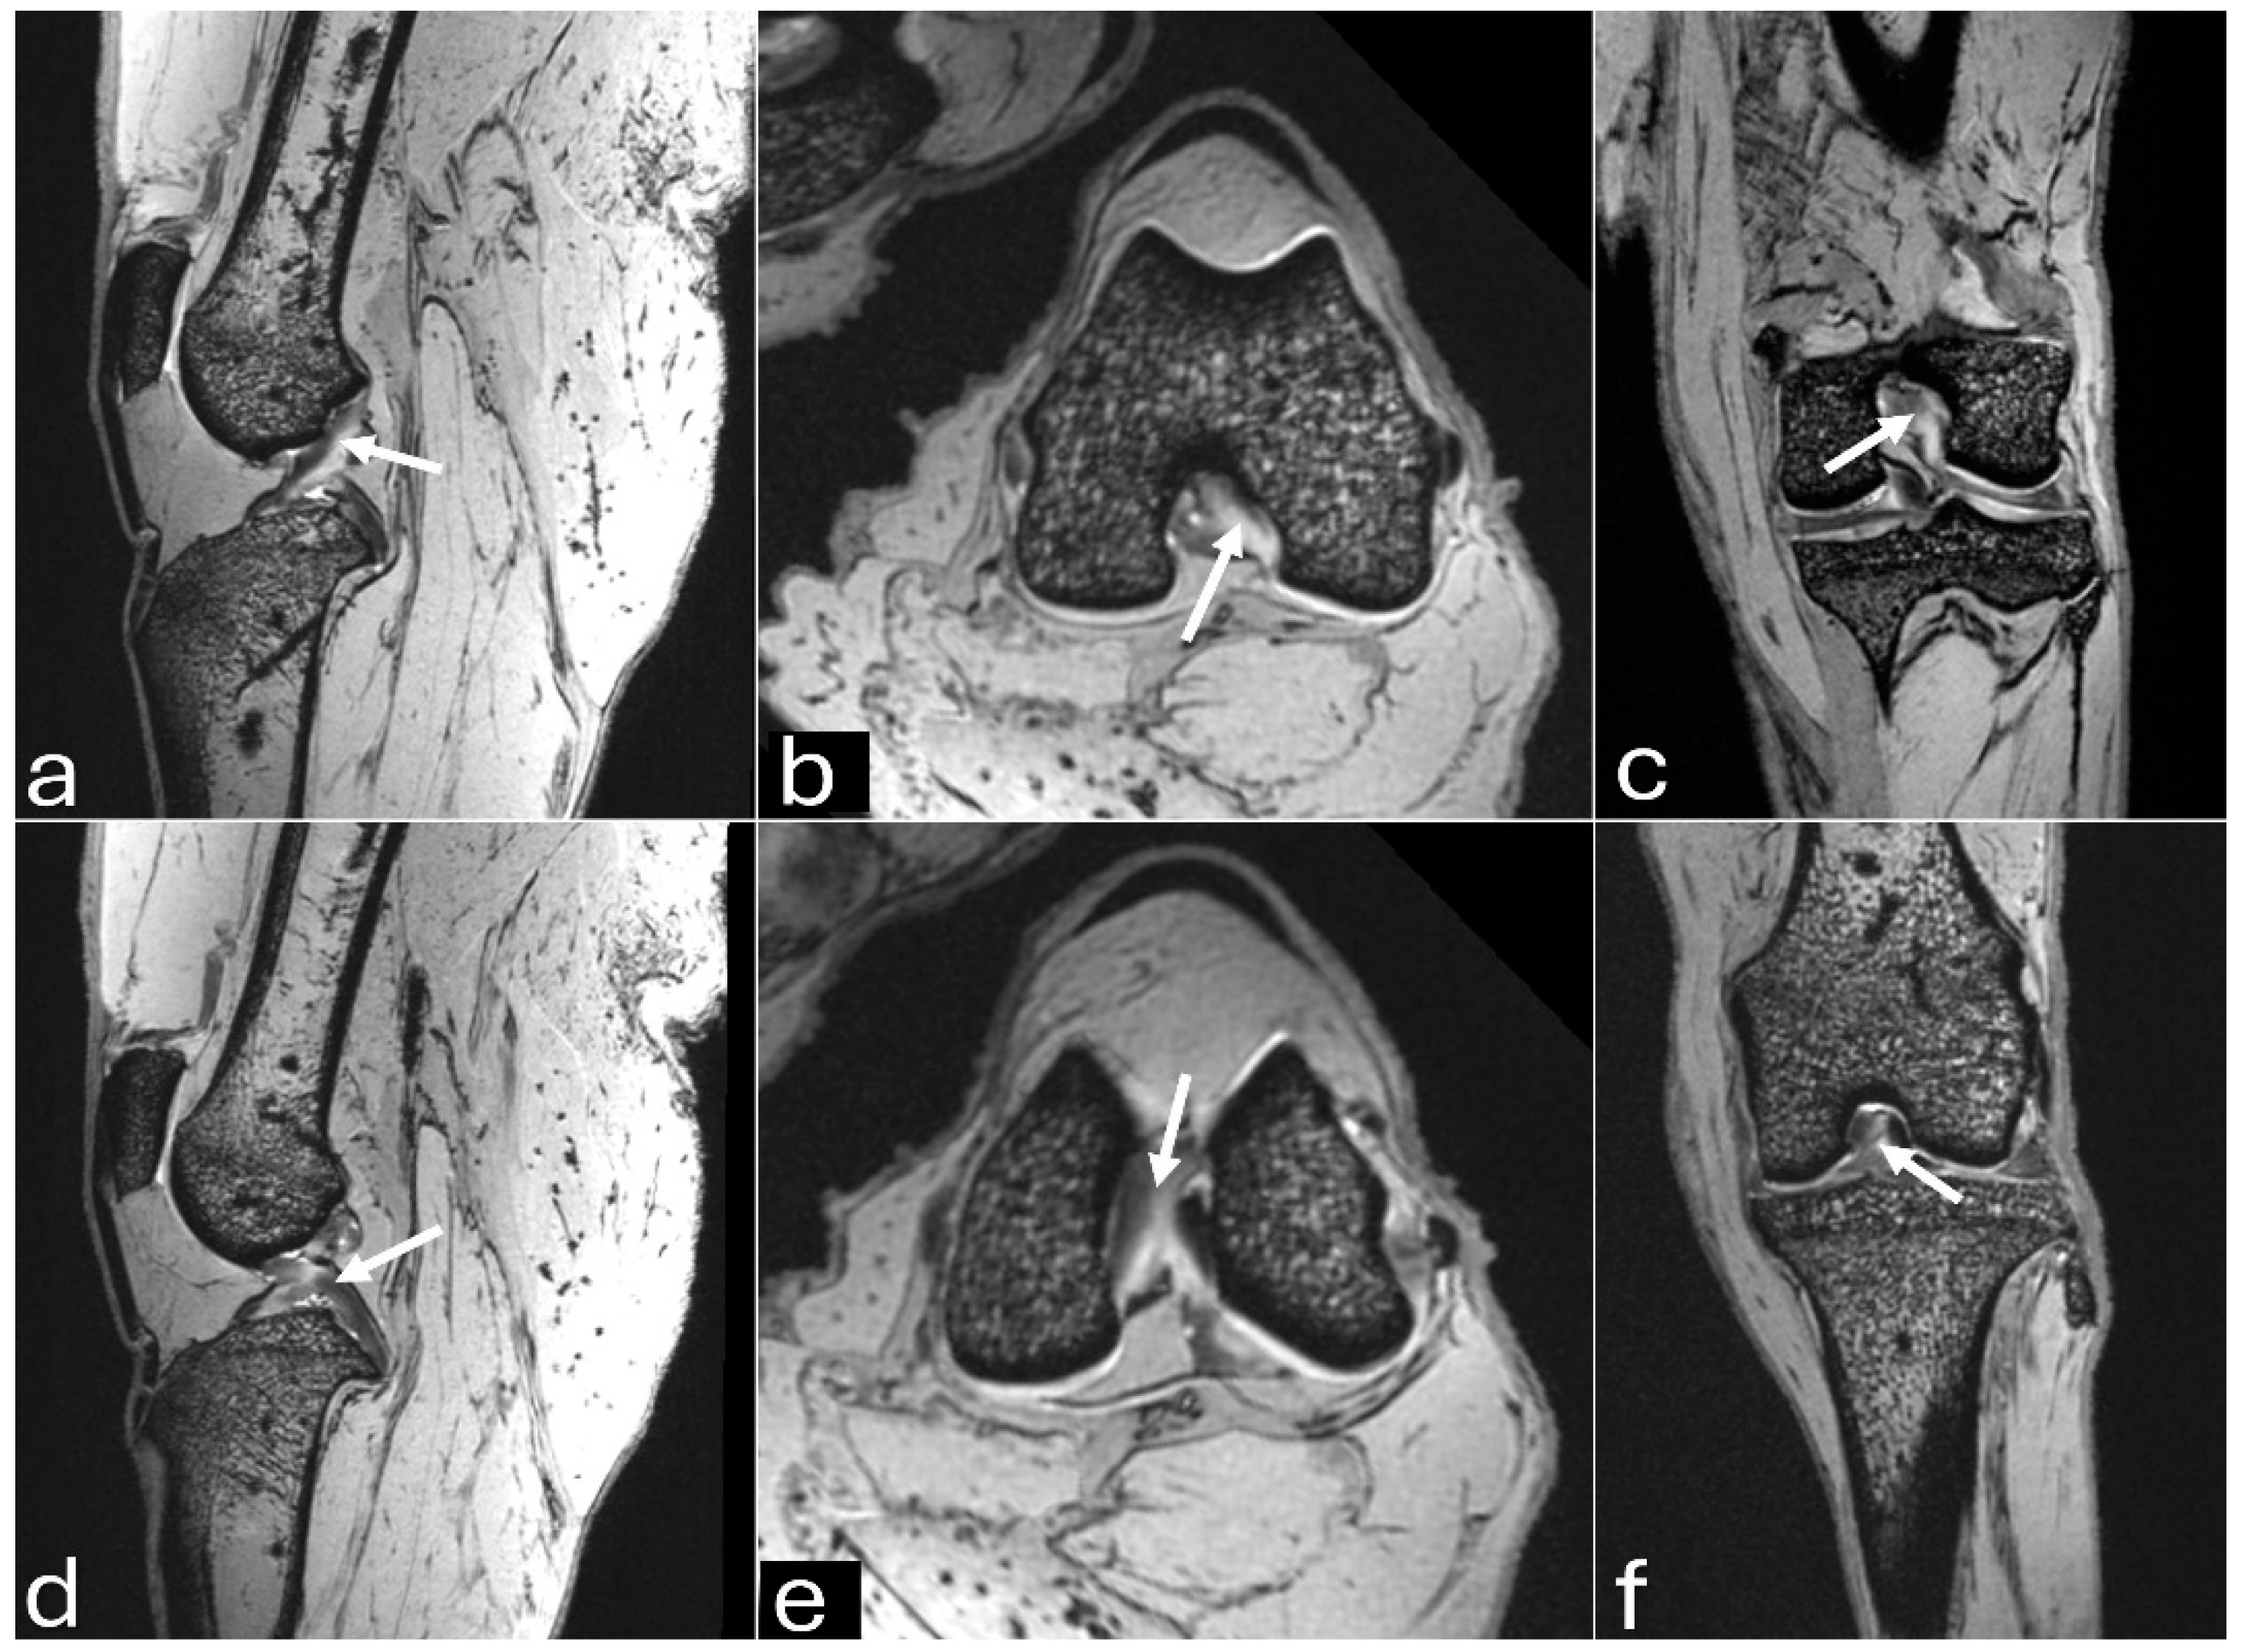

Figure 6. 3D-DESS imaging at 7-T MRI on sagittal (a, d), transversal (b, e), and dorsal (c, f) planes of an adult puma stifle joint (Puma concolor). (a, b, c) Observe the cruciate cranial ligament (arrow). (d, e, f) Note the caudal cranial ligament (arrow).

The MRI images allowed for more precise visualization of the cranial and caudal cruciate ligaments (Figure 6), the C-type shape of both menisci on the transverse plane, and the triangular appearance on the sagittal plane, with the medial meniscus being larger than the lateral one (Figure 7 and Figure 8). Mineralization was easily identified in the cranial horn of the medial meniscus as a rounded structure with a hypointense signal (3D-DESS sequence). High-resolution imaging of subchondral bone and cartilage was also visualized (Figure 9).

The meniscus and cruciate ligaments were visualized on CT and MRI, but ultra-high-field MRI (7 Tesla) allowed these structures to be observed with precision. Following FDA approval for clinical use in humans, 7 Tesla MRI has been used to diagnose meniscal injuries and changes in articular cartilage and subchondral bone due to its rapid image acquisition, high spatial resolution, and superiority in detecting early tissue changes [17,18]. No articular cartilage changes were observed in the stifle joint using DESS and FLASH sequences in the present study. Previous research in humans found similar sensitivity of FLASH and DESS sequences for longitudinal morphometry of stifle cartilage [19]. Additionally, the subchondral bone showed no changes when evaluated with the T2 sequence in the present study, which is considered the most accurate for detecting this type of injury [20].